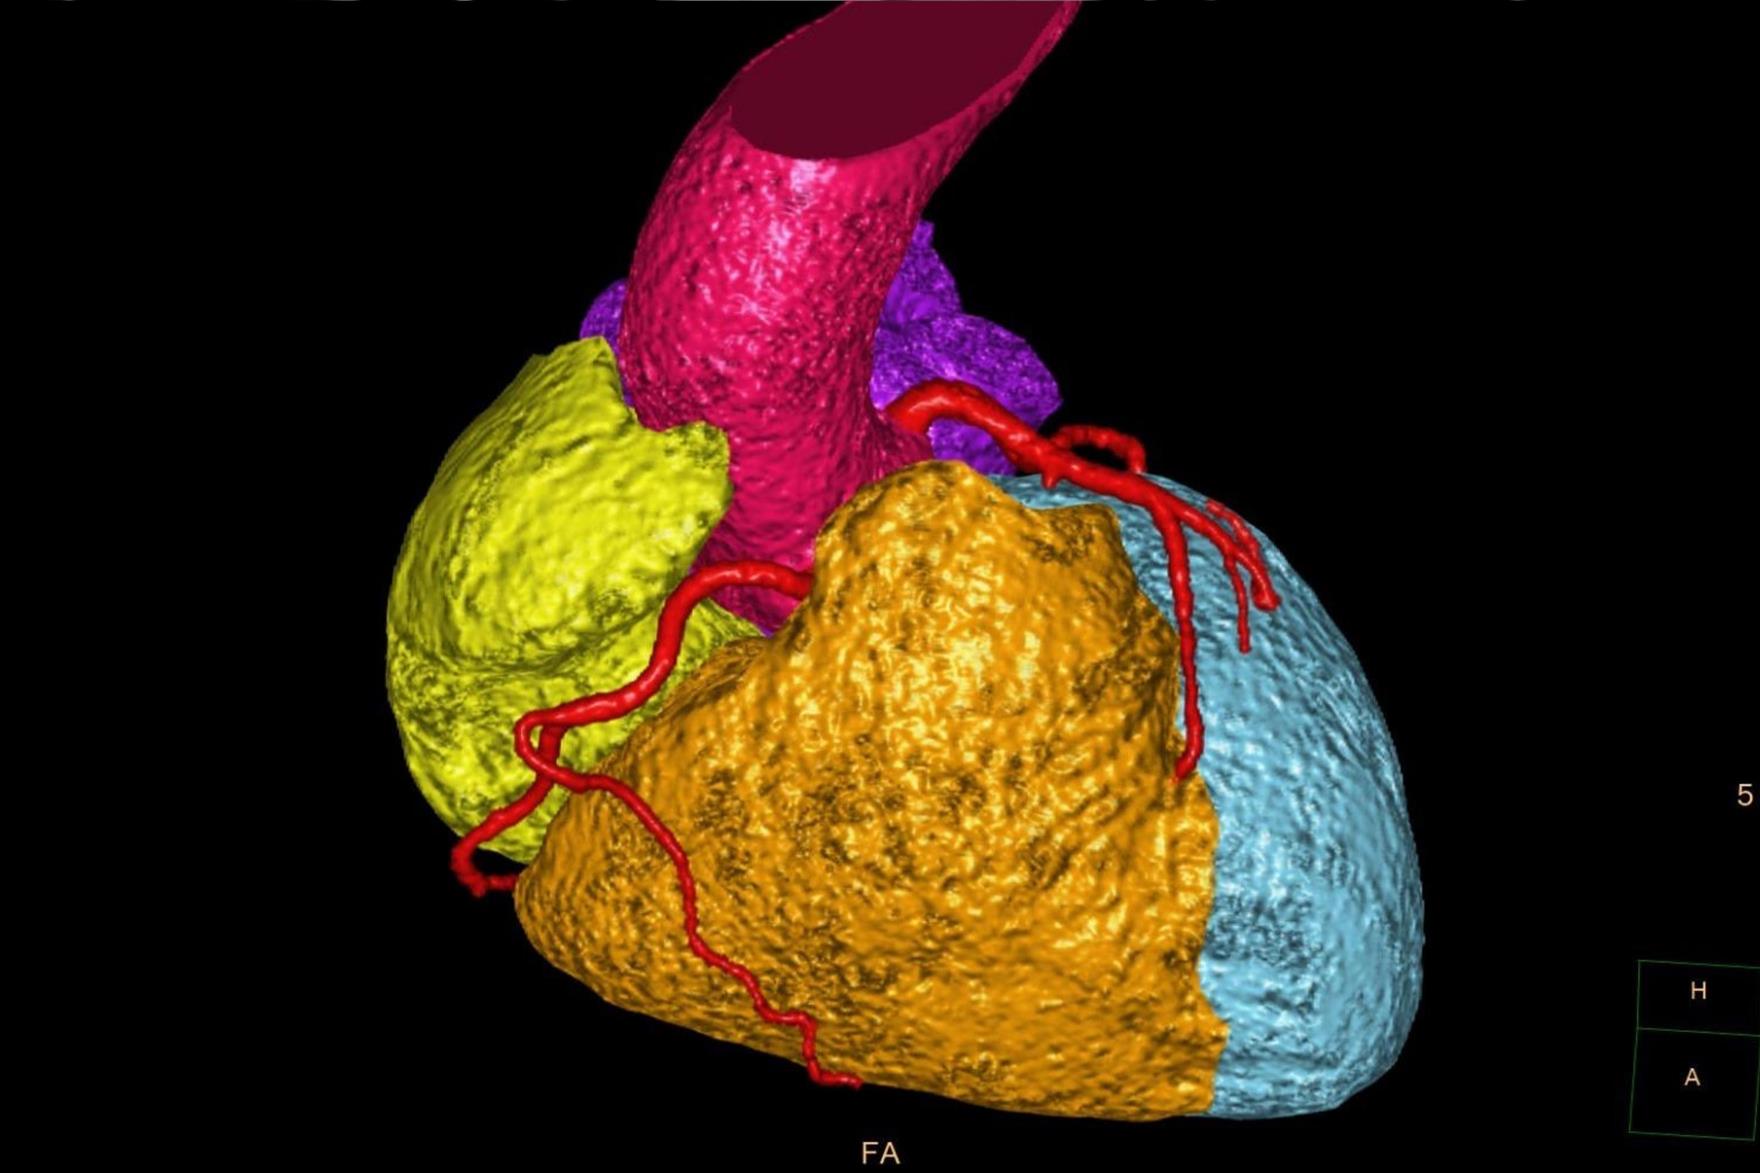

PAÜ Hastaneleri Radyoloji Anabilim Dalı Öğretim Üyesi Doç. Dr. Vefa Çakmak yaptığı açıklama da şunları söyledi: “Pandemi döneminde hayatımıza daha sık giren bilgisayarlı tomografi (BT), günümüzde tanı ve tedavi süreçlerinde hayati önem taşıyan bir görüntüleme yöntemi olarak kullanılmaya devam ediyor. Radyasyon içeren bu teknoloji, pek çok organın ayrıntılı şekilde incelenmesini sağlarken, acil durumlarda hızlı teşhis imkânı sunarak hayat kurtarıcı bir rol üstleniyor. Özellikle kanserin tanı ve takibinde, trafik kazaları, beyin kanamaları, kırıklar ve büyük cerrahiler öncesinde önemli bir yer tutuyor. BT ile kalbi besleyen damarların detaylı şekilde görüntülenmesi mümkün hale geliyor. Halk arasında ‘sanal anjiyo’ olarak bilinen bu yöntemle, kalpte işlem gerektiren damar tıkanıklıkları erkenden saptanabiliyor. Böylece hastalar, gereksiz klasik anjiyo işlemlerinden korunuyor. Aynı anda kalp duvarları, kalp içindeki pıhtı ya da tümör gibi oluşumlar ve ritim bozukluğuna neden olabilecek yapılar da değerlendirilebiliyor. Ayrıca, bu çekimler sırasında düşük dozla akciğer görüntülemesi de yapılarak yapısal akciğer hastalıkları, akciğer kanserleri ve göğüs kafesiyle ilgili kemik problemleri de tespit edilebiliyor. Çekim öncesinde hastanın böbrek fonksiyonlarını korumak amacıyla kreatin ve GFR gibi kan testleri yapılıyor. Hastanın mevcut hastalık öyküsü ve ilaç alerjileri sorgulanıyor. Kaliteli bir görüntü elde edebilmek için kalp atım hızının dakikada 70 civarına düşürülmesi gerekebiliyor; bu durumda nabız düzenleyici ilaçlar kullanılabiliyor. İşlem sırasında hasta monitörize ediliyor, göğüs bölgesindeki metal eşyalar çıkarılıyor ve yaklaşık 10–15 saniyelik nefes tutması isteniyor. Kardiyak BT çekimi 4–10 saniye sürüyor ve görüntülerin değerlendirilip raporlanması genellikle aynı gün içinde tamamlanıyor.”

Bu yöntemin hastada kalp hastalığı, damar tıkanıklığı, akciğer hastalığı veya kanser gibi önemli durumların varlığını veya yokluğunu göstermesi açısından büyük fayda sağladığına değinen Doç. Dr. Vefa Çakmak sözlerine şöyle devam etti: “Özellikle sigara kullanan bireylerde, akciğerin bu durumdan ne derece etkilendiği açıkça görülebiliyor. Böylece, sigara bağımlılarının sıkça sorduğu ‘Acaba kanser miyim?’ sorusuna yanıt bulunmuş oluyor. Uygulamanın herhangi bir zararı bulunmuyor ve kullanılan teknoloji uluslararası standartlara uygun şekilde çalışıyor. Kalp hastalıklarının tanısında bir diğer önemli yöntem olan Kardiyak MR ise, anjiyografi ile tanı konulamayan durumlarda devreye giriyor. Kalp duvarlarının yapısal hastalıkları, kalp kapakçıklarıyla ilgili problemler, demir birikimi gibi daha özel durumların tanı ve takibi için tercih ediliyor. Bu yöntemde radyasyon bulunmuyor. Yaklaşık 25–30 dakika süren bu görüntüleme sırasında hastanın üzerindeki metal eşyalar çıkarılıyor, monitörize ediliyor ve nefes tutma komutlarına uyumu sağlanıyor. Çekim, ilgili hekim istemi doğrultusunda gerçekleştiriliyor ve sonuçlar genellikle bir iş günü içinde hastaya ulaştırılıyor. Hem BT hem de Kardiyak MR görüntülemeleri, uzman ekipler tarafından gerçekleştiriliyor ve elde edilen veriler, tanı sürecinde oldukça değerli bilgiler sunuyor. Bu teknolojiler sayesinde, birçok hastalık erken dönemde saptanabiliyor; gereksiz girişimlerin önüne geçiliyor ve hasta güvenliği en üst düzeyde tutuluyor.”